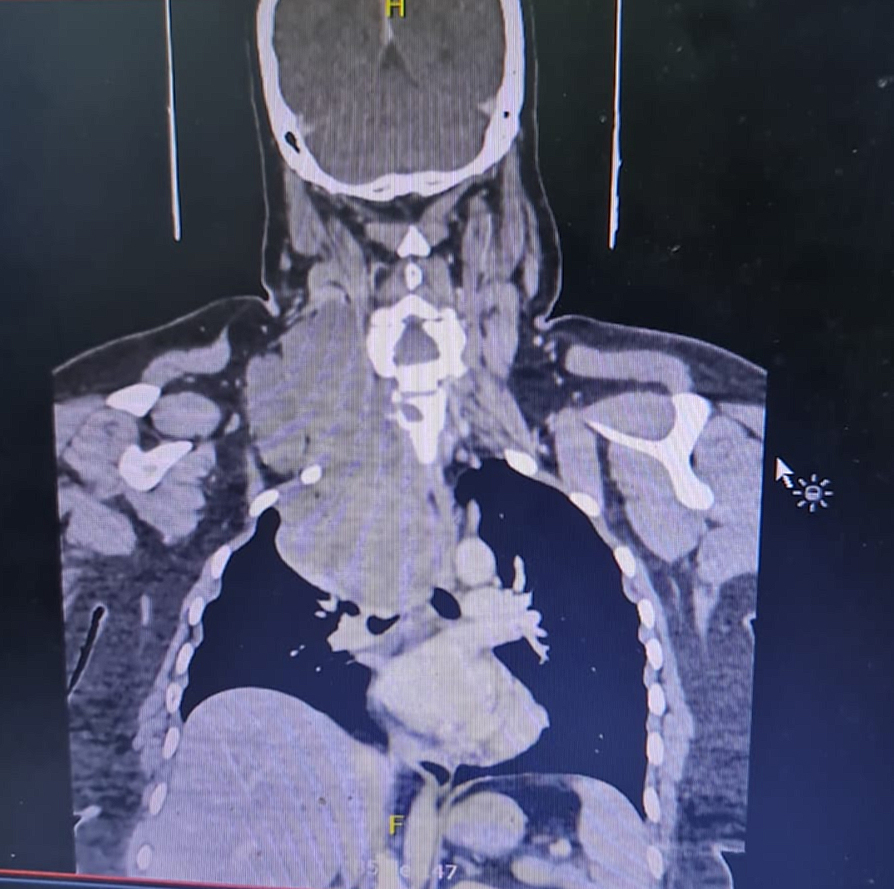

El bulto había crecido de forma lenta pero constante. Tras la consulta, se le realizó un estudio de imágenes. Allí se confirmó una tumoración que iba desde la vértebra cervical 3 hasta la torácica 5. Una biopsia posterior confirmó el diagnóstico: mixoma de la vaina de nervio periférico. Una cirugía de alta complejidad.

Durante la operación, los médicos encontraron un tumor de unos 20 centímetros de largo y 10 de diámetro. Era de forma irregular y bordes poco definidos. Estaba ubicado en la parte lateral del cuello, entre los músculos escalenos, pegado a la vena yugular interna con afectación de la vértebra cervical 7 y torácica 1 con invasión del canal medular. Además, llegaba hasta el tórax, cerca de la tráquea, y estaba firmemente adherido al plexo braquial derecho.